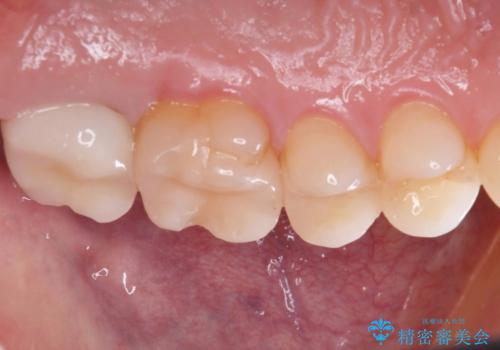

銀歯が綺麗な白い歯になりました。

適合がとてもよいので、フロスの引っかかりも解消されました。